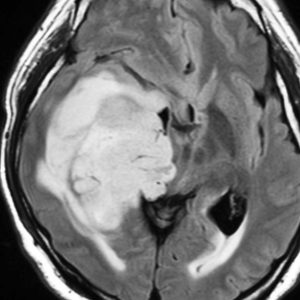

右側頭葉島の病変です。1年間の経過ではっきり増大したので,無症状でしたが生検術を行いました。病理組織では,異型グリアの増殖はありましたが,核分裂蔵,血管内皮の増生や壊死は明らかではありませんでした。しかし,遺伝子診断ではIDH1/2 野生型,ATRX retained,TERT promotor野生型,1p/19q共欠失なしでした。膠芽腫という確定病理診断です。

標準治療を加えましたが,数ヶ月後に急激な増大を呈しました。グレード4の臨床像です。MRI画像よりも病理組織像よりも,遺伝子診断の方がより性格に予後を示す例です。